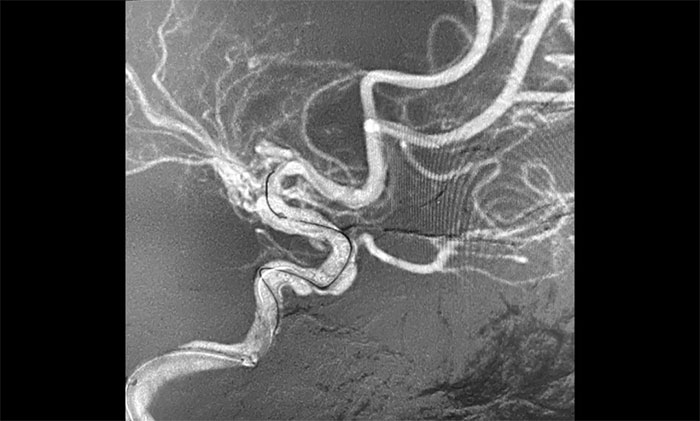

接下來,左頸內動脈海綿竇段、床突段多發(fā)動脈瘤處理極具挑戰(zhàn)。由于C5、C6、C7段血管極度迂回曲折,類似“N”形,從C4、C5到C6之間的血管約成45°銳角,從C6至C7之間又是約30°銳角,可謂“山路十八彎”,而導絲又是極軟,每向前推進一毫米,都非常艱難。這種介入手術對術者的技術要求非常高,如果支架貼合不好,打開不良,還需要用導絲蠕動“按摩”,讓支架重新回到血管壁上。

▲ 血管極度迂曲,為手術帶來挑戰(zhàn)